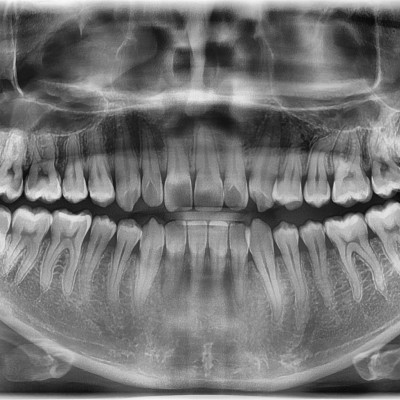

#18,28,38,48 사랑니 발치 #18,28,38,48 사랑니 발치 구강 외과 전문의가 당일 발치했습니다. --------------------..

작성자 이턱이 작성일 02-09 조회 48